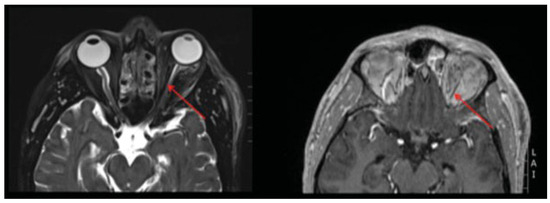

Immediately following decompression, the patient was noted to have a persistent afferent pupillary defect OS. Intraocular pressures were 11 mm Hg OD and 38 mm Hg OS. High-dose steroids were initiated to assist with edema control. The intraocular pressure in the left eye continued to improve following decompression and was 15 mm Hg 8 h after decompression. He continued to be examined serially by the surgical and ophthalmology teams. There was no improvement in light perception in the left eye. A subsequent magnetic resonance angiogram, taken on postoperative day 1, demonstrated infarction of the left optic nerve (Figure 5). The patient subsequently underwent bony decompression of the optic canal. He was followed and had no recovery of visual acuity at 6 months postdecompression (20/400 OS).

Figure 5. Postdecompression magnetic resonance angiography. T2-weighted image (left) and fat saturated image (right) infarction of the optic nerve (arrows).